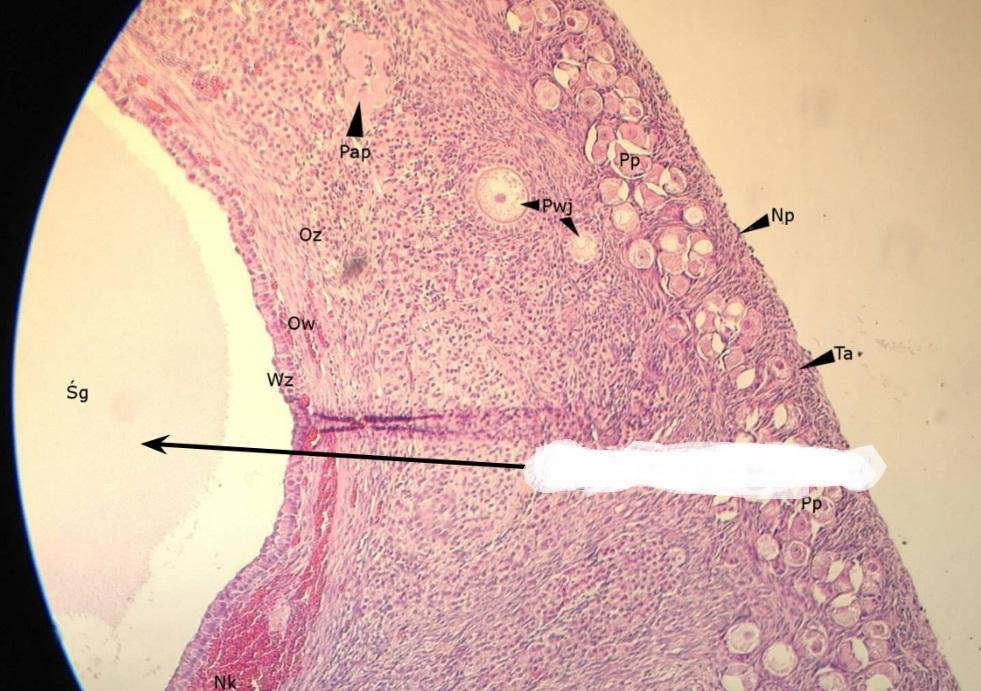

nabłonek sześcienny - płciowy (jajnik, kora)

Pytanie 470

pęcherzyk jajnikowy pierwotny (jajnik, kora)

Pytanie 471

pęcherzyk wzrastający bezjamisty (jajnik, kora)

Pytanie 472

pęcherzyki dojrzewające jamiste (jajnik, kora)

Pytanie 473

pęcherzyk Graafa (jajnik, kora)

Pytanie 474

pęcherzyk atrezyjny (jajnik, kora)

Pytanie 475

błona biaława (jajnik, kora)

Pytanie 476

gruczoły śródmiąższowe (jajnik, kora)

Pytanie 477

warstwa ziarnista pęcherzyka (jajnik, kora)

Pytanie 478

osłonka wewnętrzna - obfita w komórki (jajnik, kora)

Pytanie 479

osłonka zewnętrzna - z dużą ilością włókien (jajnik, kora)

Pytanie 480